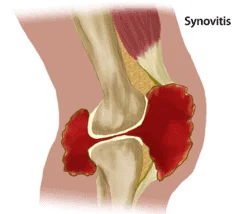

Sinovitis kolena

Sinovitis kolena je upala kolena, za mnoge je to voda u kolenu. Izraz voda u kolenima često se koristi i za opisivanje drugih stanja kolena, bilo da su povrede ili neka oboljenja praćena oticanjem.

Sinovitis najprostije rečeno predstavlja upalu koja izaziva bujanje resica unutrašnje membrane kolena – sinovija kolena. Radi se o zapaljenju unutrašnje membrane kolena. Sa pratećom ekscesnom produkcijom tečnosti što se prikazuje kao značajan otok kolena tj. voda u kolenu.